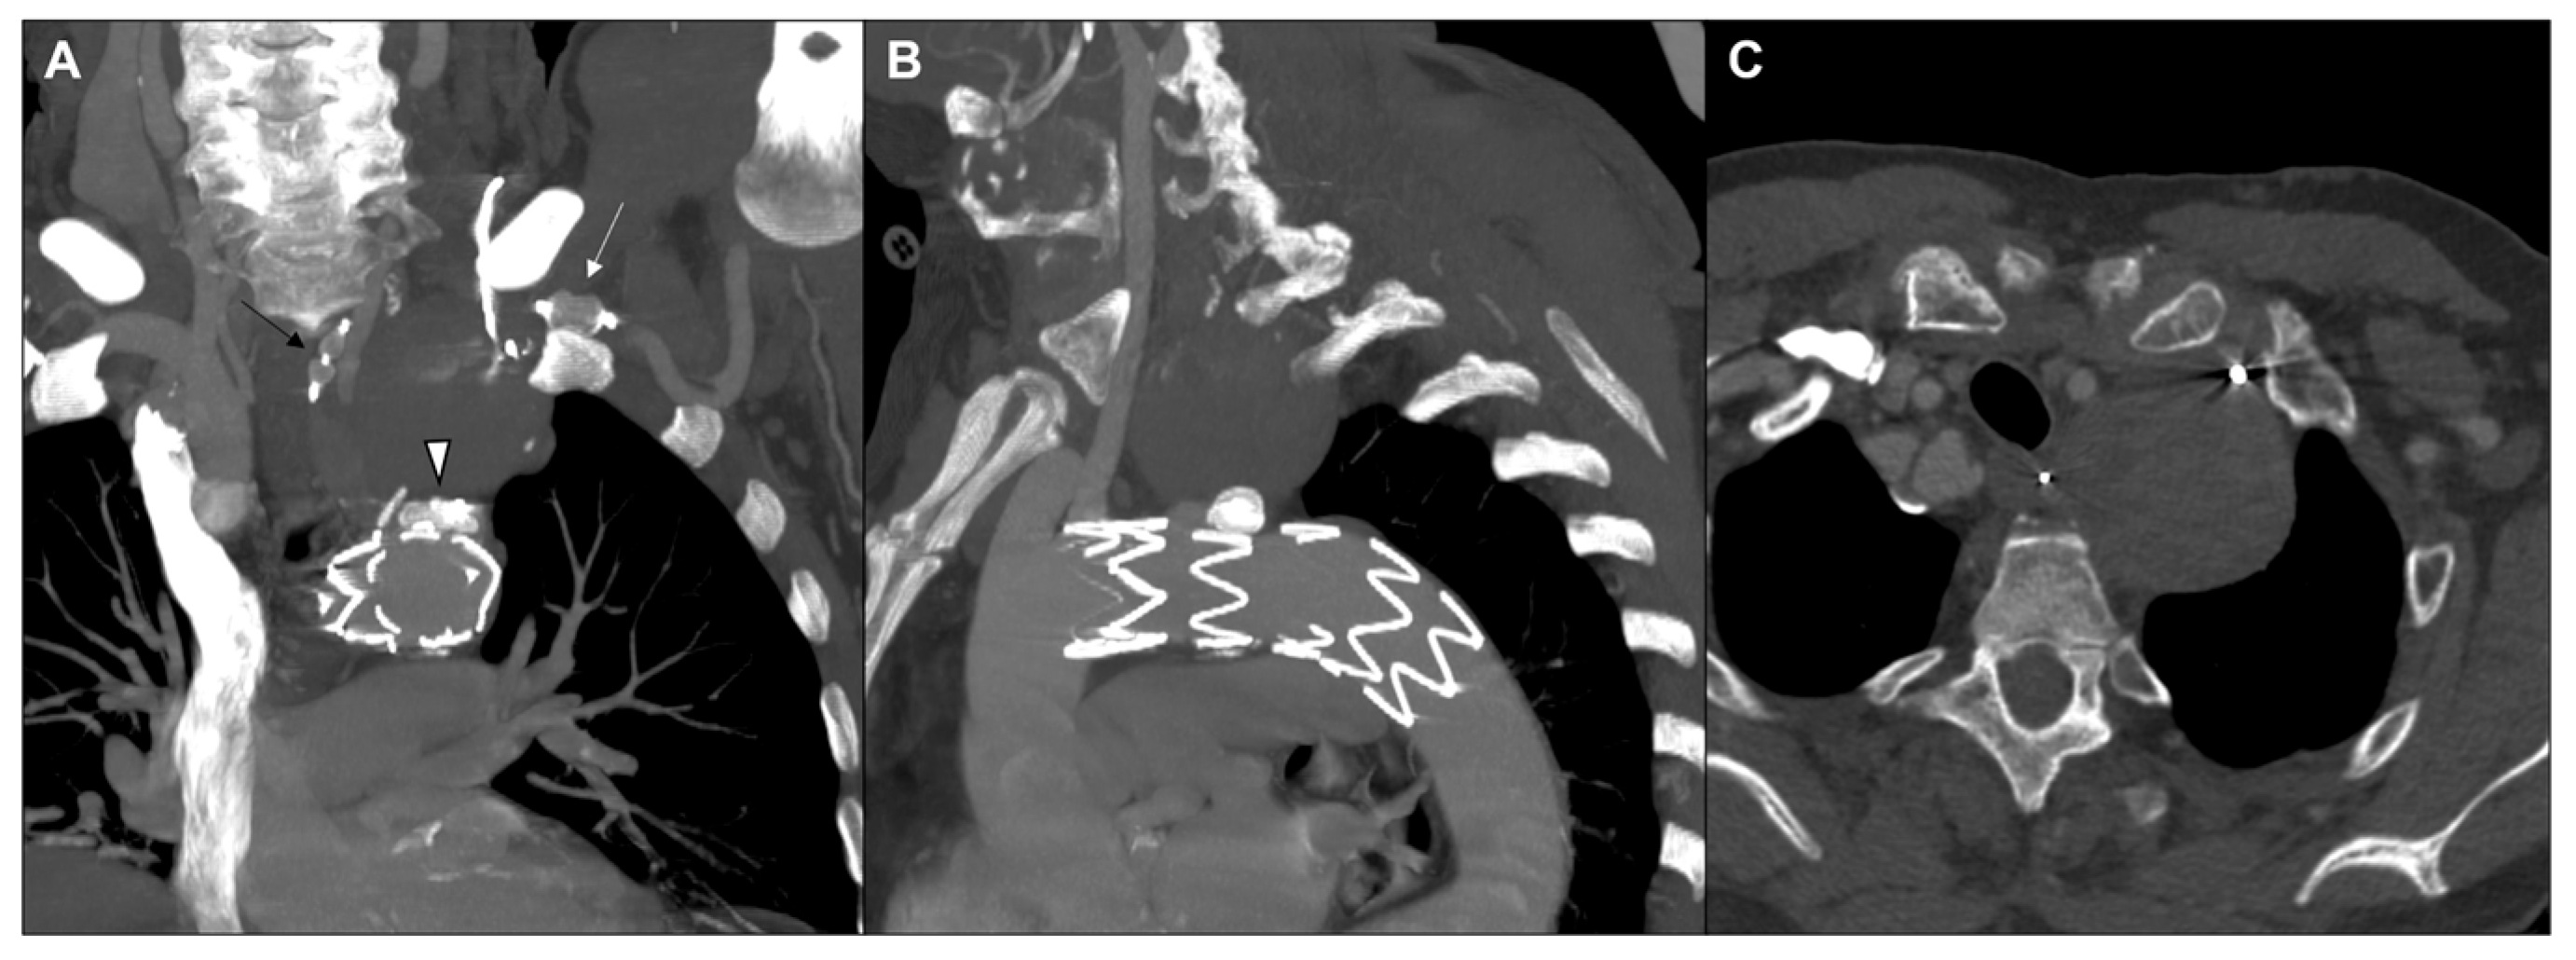

2. Case Report